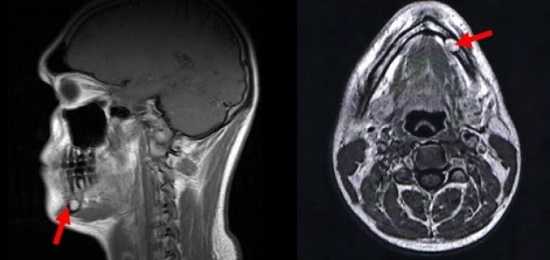

МРТ головы в сагиттальной и аксиальной проекциях, стрелка указывает на образование в области нижней челюсти